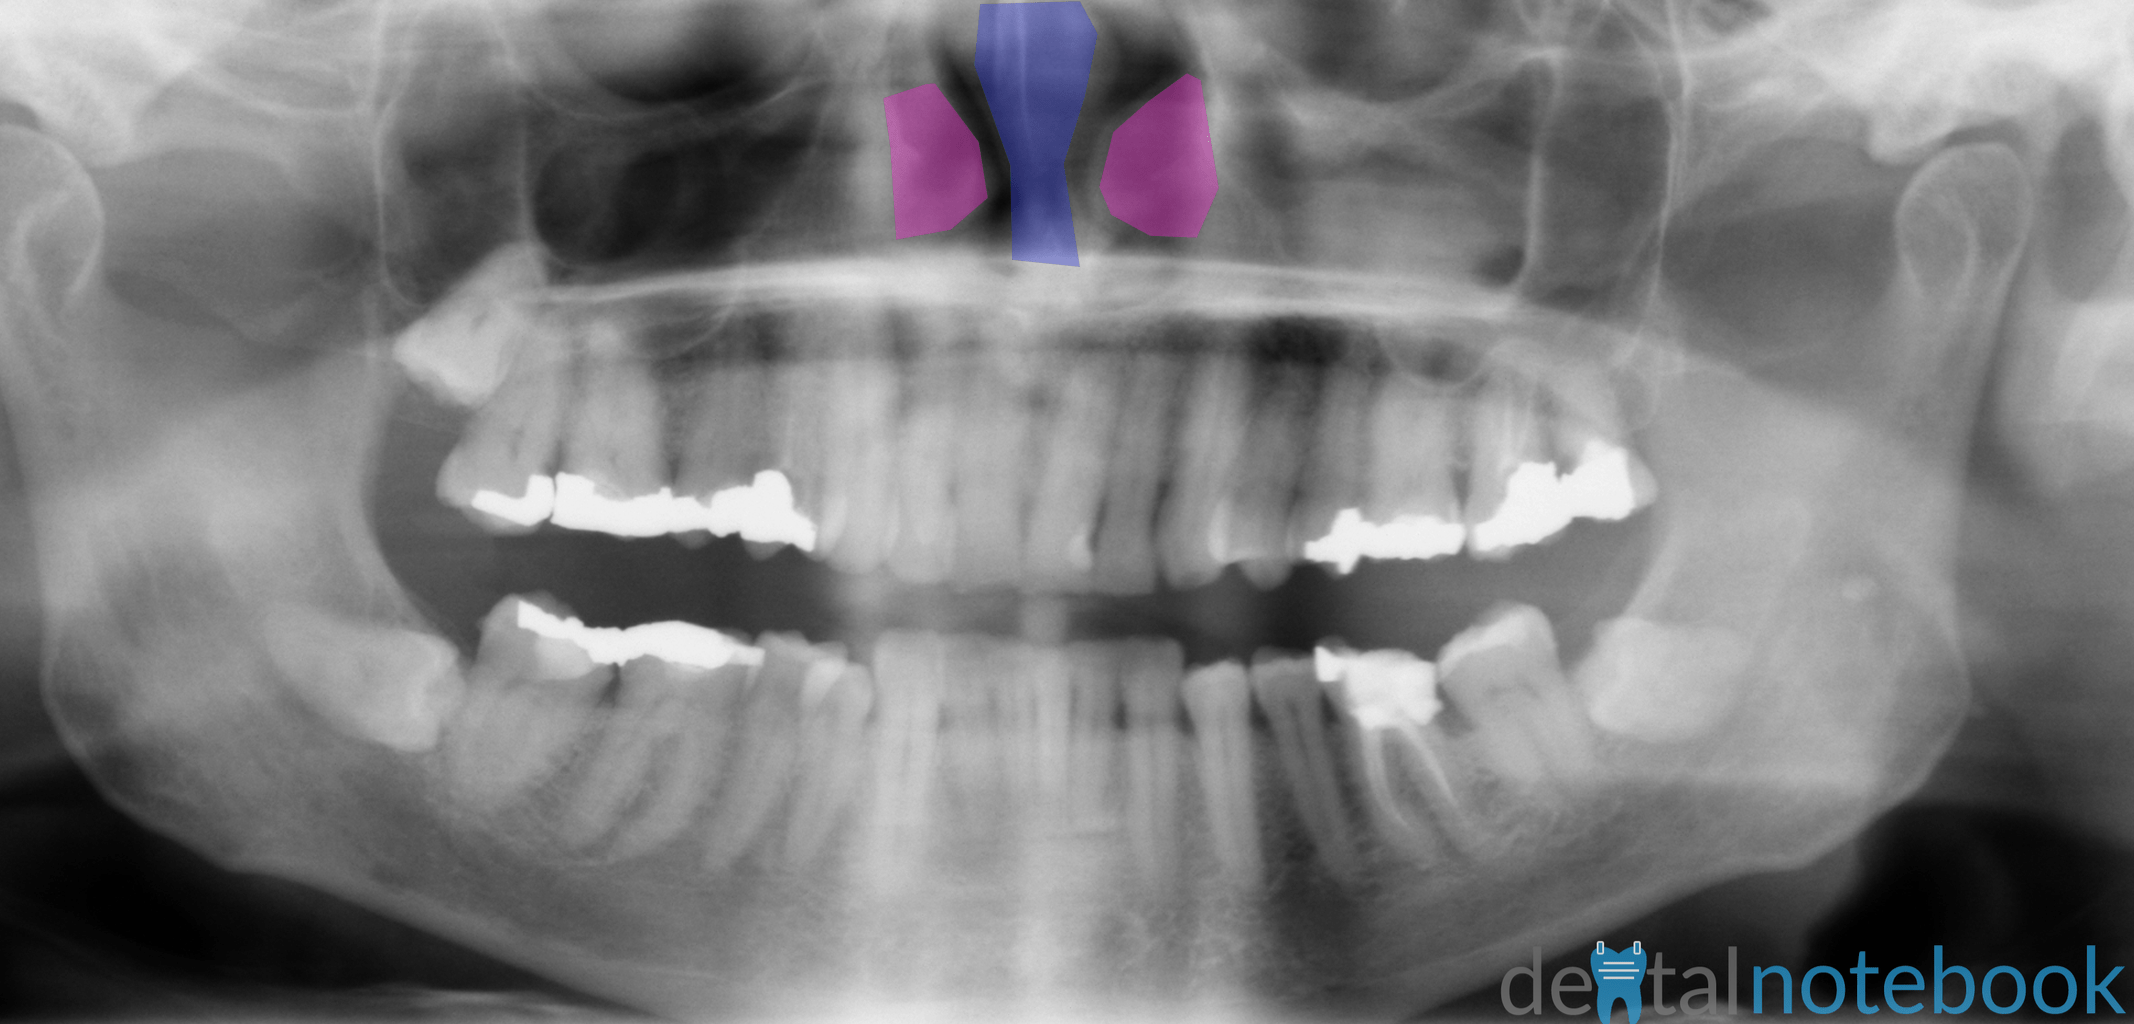

A panoramic image displays the patient’s maxillary and mandibular oral and facial structures across a flat surface. The purpose of the panoramic radiographs: Technique & anatomy review course is to provide students and clinicians with a review of. They provide an overview of the patient’s dentition as well as surrounding anatomy. 1 according to iannucci & howerton, panoramic imaging is an extraoral technique that is. Panoramic radiography has become a commonly used imaging modality in dental practice and can be a valuable diagnostic. You can see more about why we do panoramic films here. For the purposes of this course, we. These images come from interpretation of panoramic radiographs by perschbacher and oral radiology principles and interpretation by mallya and lam. It is important to understand the landmarks normally seen on panoramic images in order to prevent misdiagnosis of a radiopaque or radiolucent area.

Anatomy of Panoramic Films OPTs/DPTs/OPGs dentalnotebook